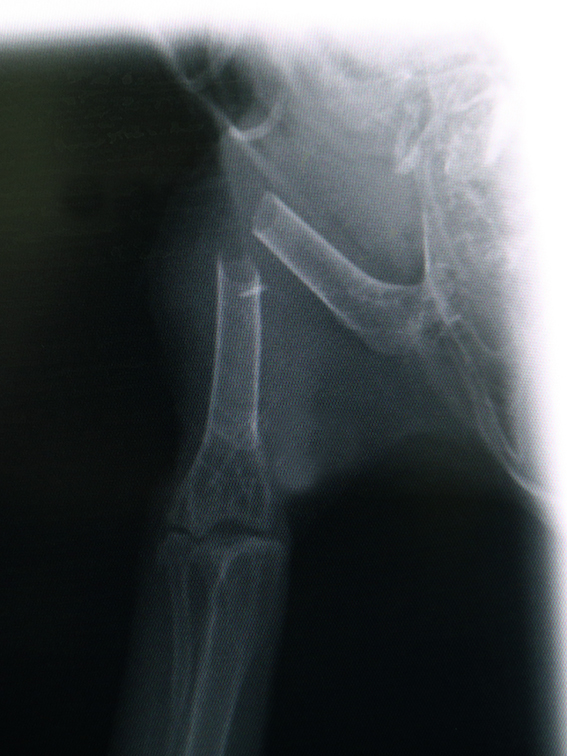

ARS bracht de gewonde uil met spoed over naar het Natuurhulpcentrum. Onze dierenverzorgers stelden een pootbreuk vast en fixeerden de poot zodat er niet meer schade zou optreden. De röntgenfoto toonde een breuk van het dijbeen, een complexe plaats om te spalken en een operatie drong zich dus op. Gelukkig waren er 2 lichtpuntjes: de vogel was nog bijzonder alert en strijdlustig én het ongeval was nog maar 48u geleden gebeurd.

Dierenartsen Stef en Matty van DAC Assist besloten om zo snel mogelijk te opereren en vandaag ging de ransuil onder het mes. Tijdens de succesvolle operatie waren er maar liefst twee metalen pinnen nodig om de poot terug in de juiste positie te krijgen. Ondertussen is de ransuil ontwaakt uit narcose en stelt hij het goed. De vogel zal nog enkele weken op de afdeling Intensieve Zorgen verblijven. Als er verder geen complicaties optreden zal de vogel daarna verhuizen naar een binnenkooi om te revalideren. Vervolgens zal de uil zijn definitieve vrijlating voorbereiden in een van onze vliegkooien...